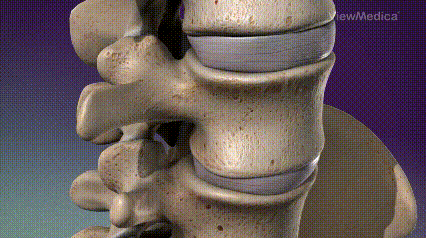

“骨水泥手术”能够快速止痛+恢复椎体高度+强化骨折椎体强度与刚度+纠正后凸畸形,主要有经皮椎体成形术(PVP)经皮后凸成形术(PKP)

图:PKP和PVP示意图“骨水泥手术”是怎么做的呢?西安市第三医院脊柱外科江伟主任团队通过GIF动图为您介绍如下“骨水泥手术”  Step By Step